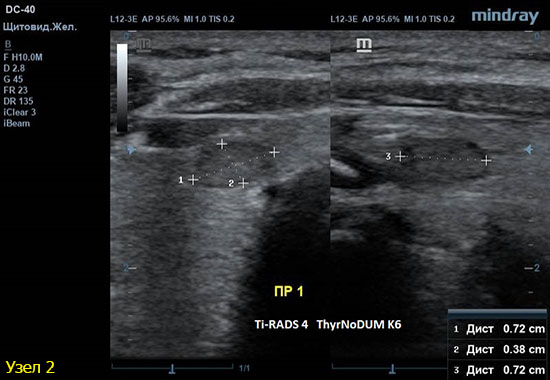

3) Узел правой доли, не прорастает капсулу щитовидной железы (0 баллов), больше широкий чем высокий (0 баллов), не имеет кальцинатов (0 баллов), с ровным четким контуром (0 баллов), изоэхогенный (1 балл), смешанной структуры (1 балл). Количество баллов 2, ACRTi-RADS2, ThyrNoDUMК1. Пункция не показана в связи с низким риском.